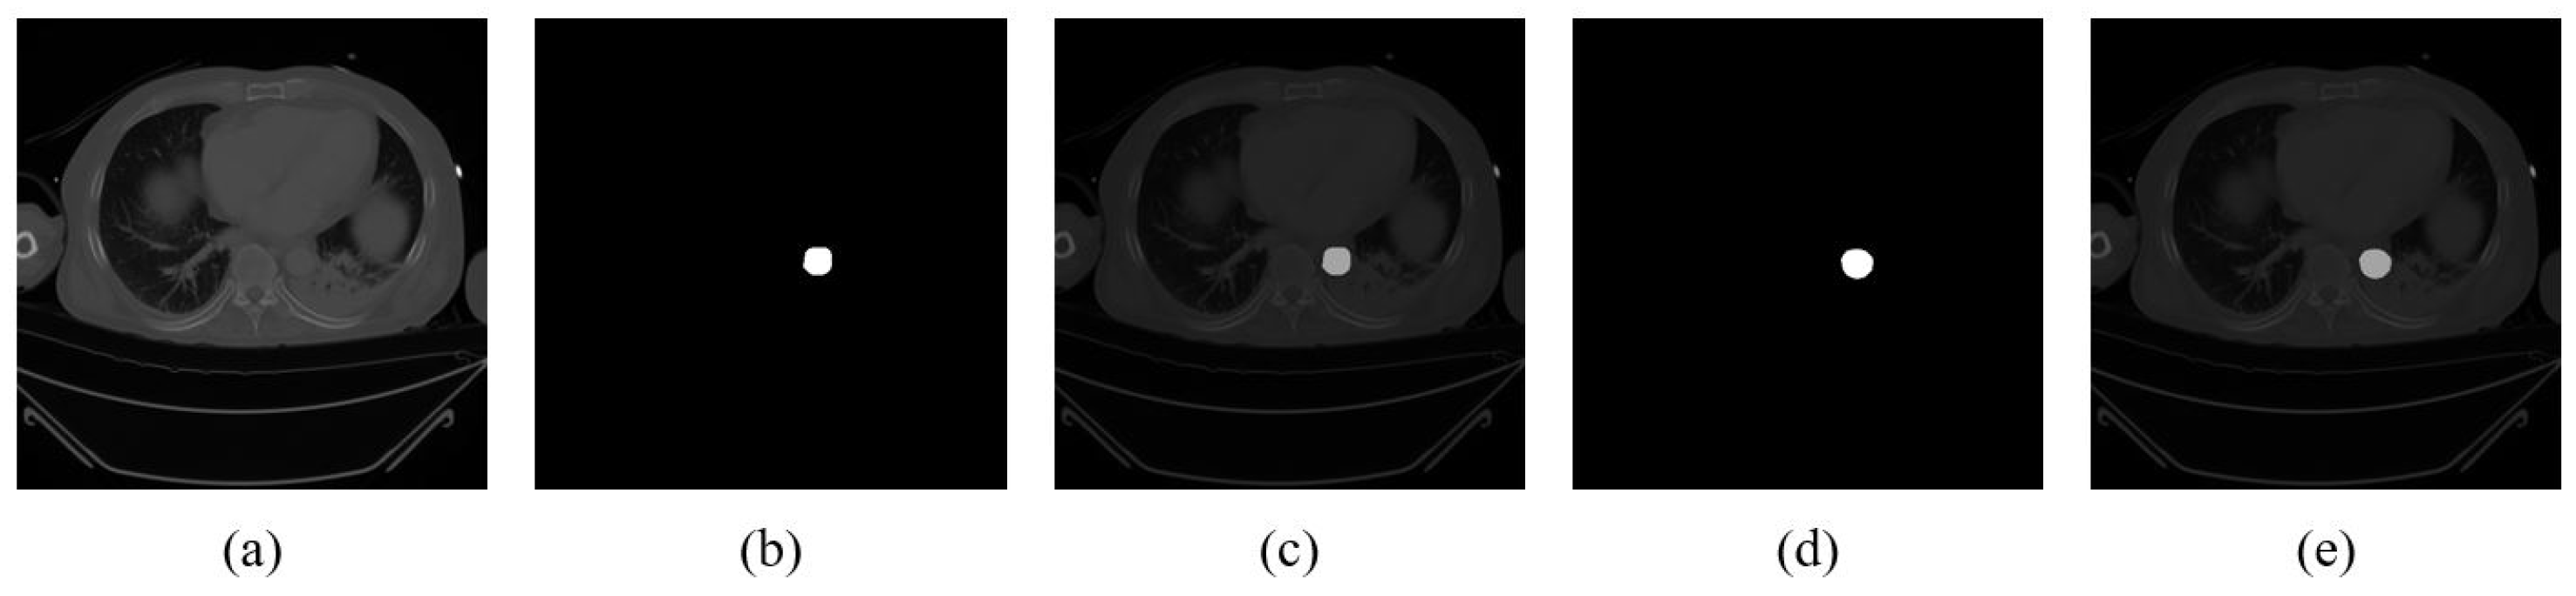

2.4. Ellipse Fitting of the Aorta